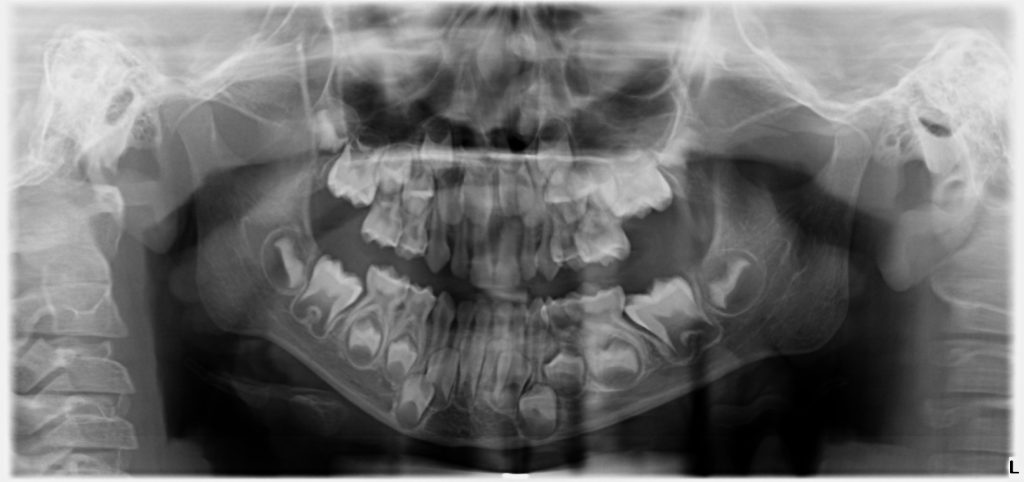

Bu sebeple bu hastamızdan da hasta velilerine “çene filmi” dediğimiz, panoramik çene grafisi istedik. Hasta velisi için görünüşte 1 tane zannedilen çürüğün aslında, 8 süt azı dişinin 8’inde de olduğunu görmüş olduk. Süt dişi çürükleri çok hızlı ilerlediği ve sinirleri daha yüzeye yakın olduğundan hemen ağrı yaptıkları için, bu çürüklere de tedavi planladık.

Özellikle genel anestezi altında diş tedavisi yapmayı planladığımız hastalarımızda tedavi planlarken, dişin düşmesine ne kadar süre kaldığı bizim için çok önemli bir faktör. Burada bu tatlı kız çocuğu 5 yaşında ve ikinci süt azısının düşmesine 7 yıl, birinci süt azısının düşmesine 4 yıl var. Bu süre içerisinde çocuğun dişinin, dolgu olmayan diş yüzeylerinden tekrar çürümesini istemeyiz. Çünkü böyle bir durumda, çocuğunuz tekrar koltukta işlem yaptırmayabilir, yine korkabilir ve yeniden genel anestezi altında diş tedavisine ihtiyaç duyulabilir. Böyle bir durumla karşılaşmamak için, bizim için pedodontide altın standart olan, kızlar için “simli diş” erkekler için “demir adam” dişi dediğimiz paslanmaz çelik kaplamalar imdadımıza yetişiyor. Böylelikle çocuğunuzun dişlerinin diğer yüzeylerden çürümesinin de önüne geçmiş oluyoruz. Bu vakada da böyle yaptık. Okuduğunuz için teşekkürler.